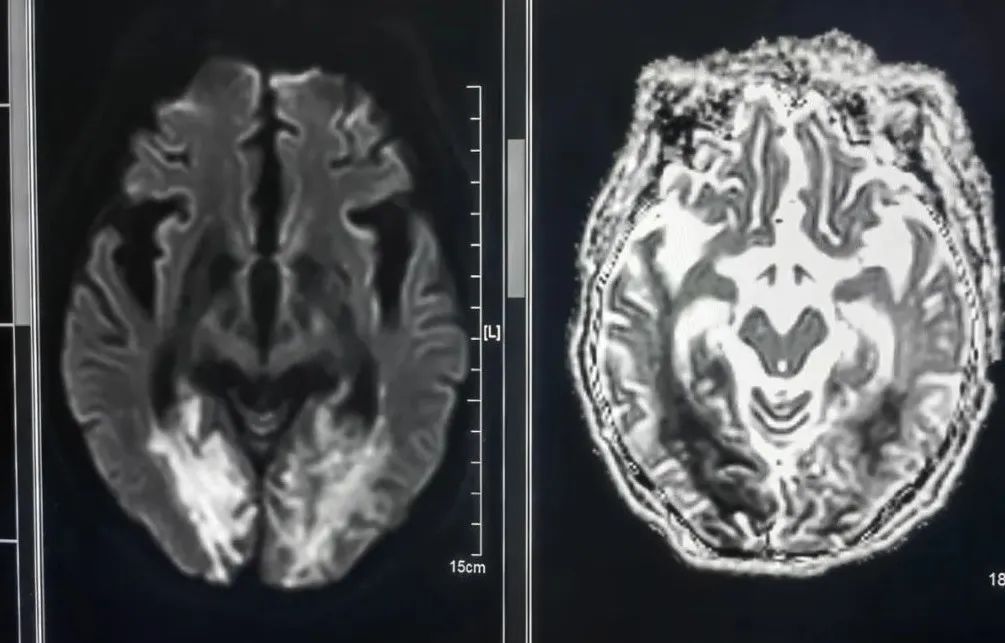

弥散成像(DWI)

DWI可以比作急性期脑缺血的“侦察兵”。能明显早于常规MRI平扫数小时发现脑缺血迹象,是脑缺血疾病筛查的项目之一。